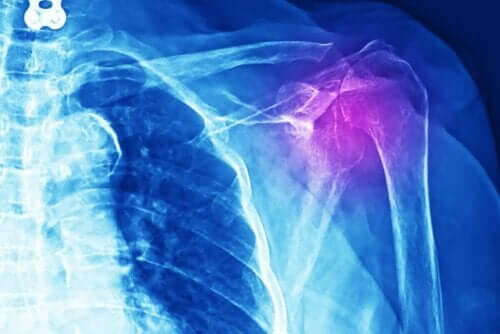

Artsen moeten verschillende tests uitvoeren om dit soort problemen correct te diagnosticeren. Het kan een röntgenfoto zijn, een echografie, een MRI of een computergestuurde axiale tomografie (CT-scan). Bovendien moeten ze een medisch bewegingsonderzoek doen en een gedetailleerd beeld krijgen van de voorgeschiedenis van de patiënt.